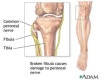

비골 근위부만의 골절은 드뭅니다.

대부분은 경골 골절, 무릎 측부인대 손상, 발목 손상 등의 다른 손상들과 동반됩니다.

크게 비골두 골절, 비골경 골절로 나눌 수 있습니다.

비골 근위부 부위의 부종과 압통이 관찰됩니다.

영상 검사

무릎의 AP & lateral view 외에 oblique view를 시행합니다.